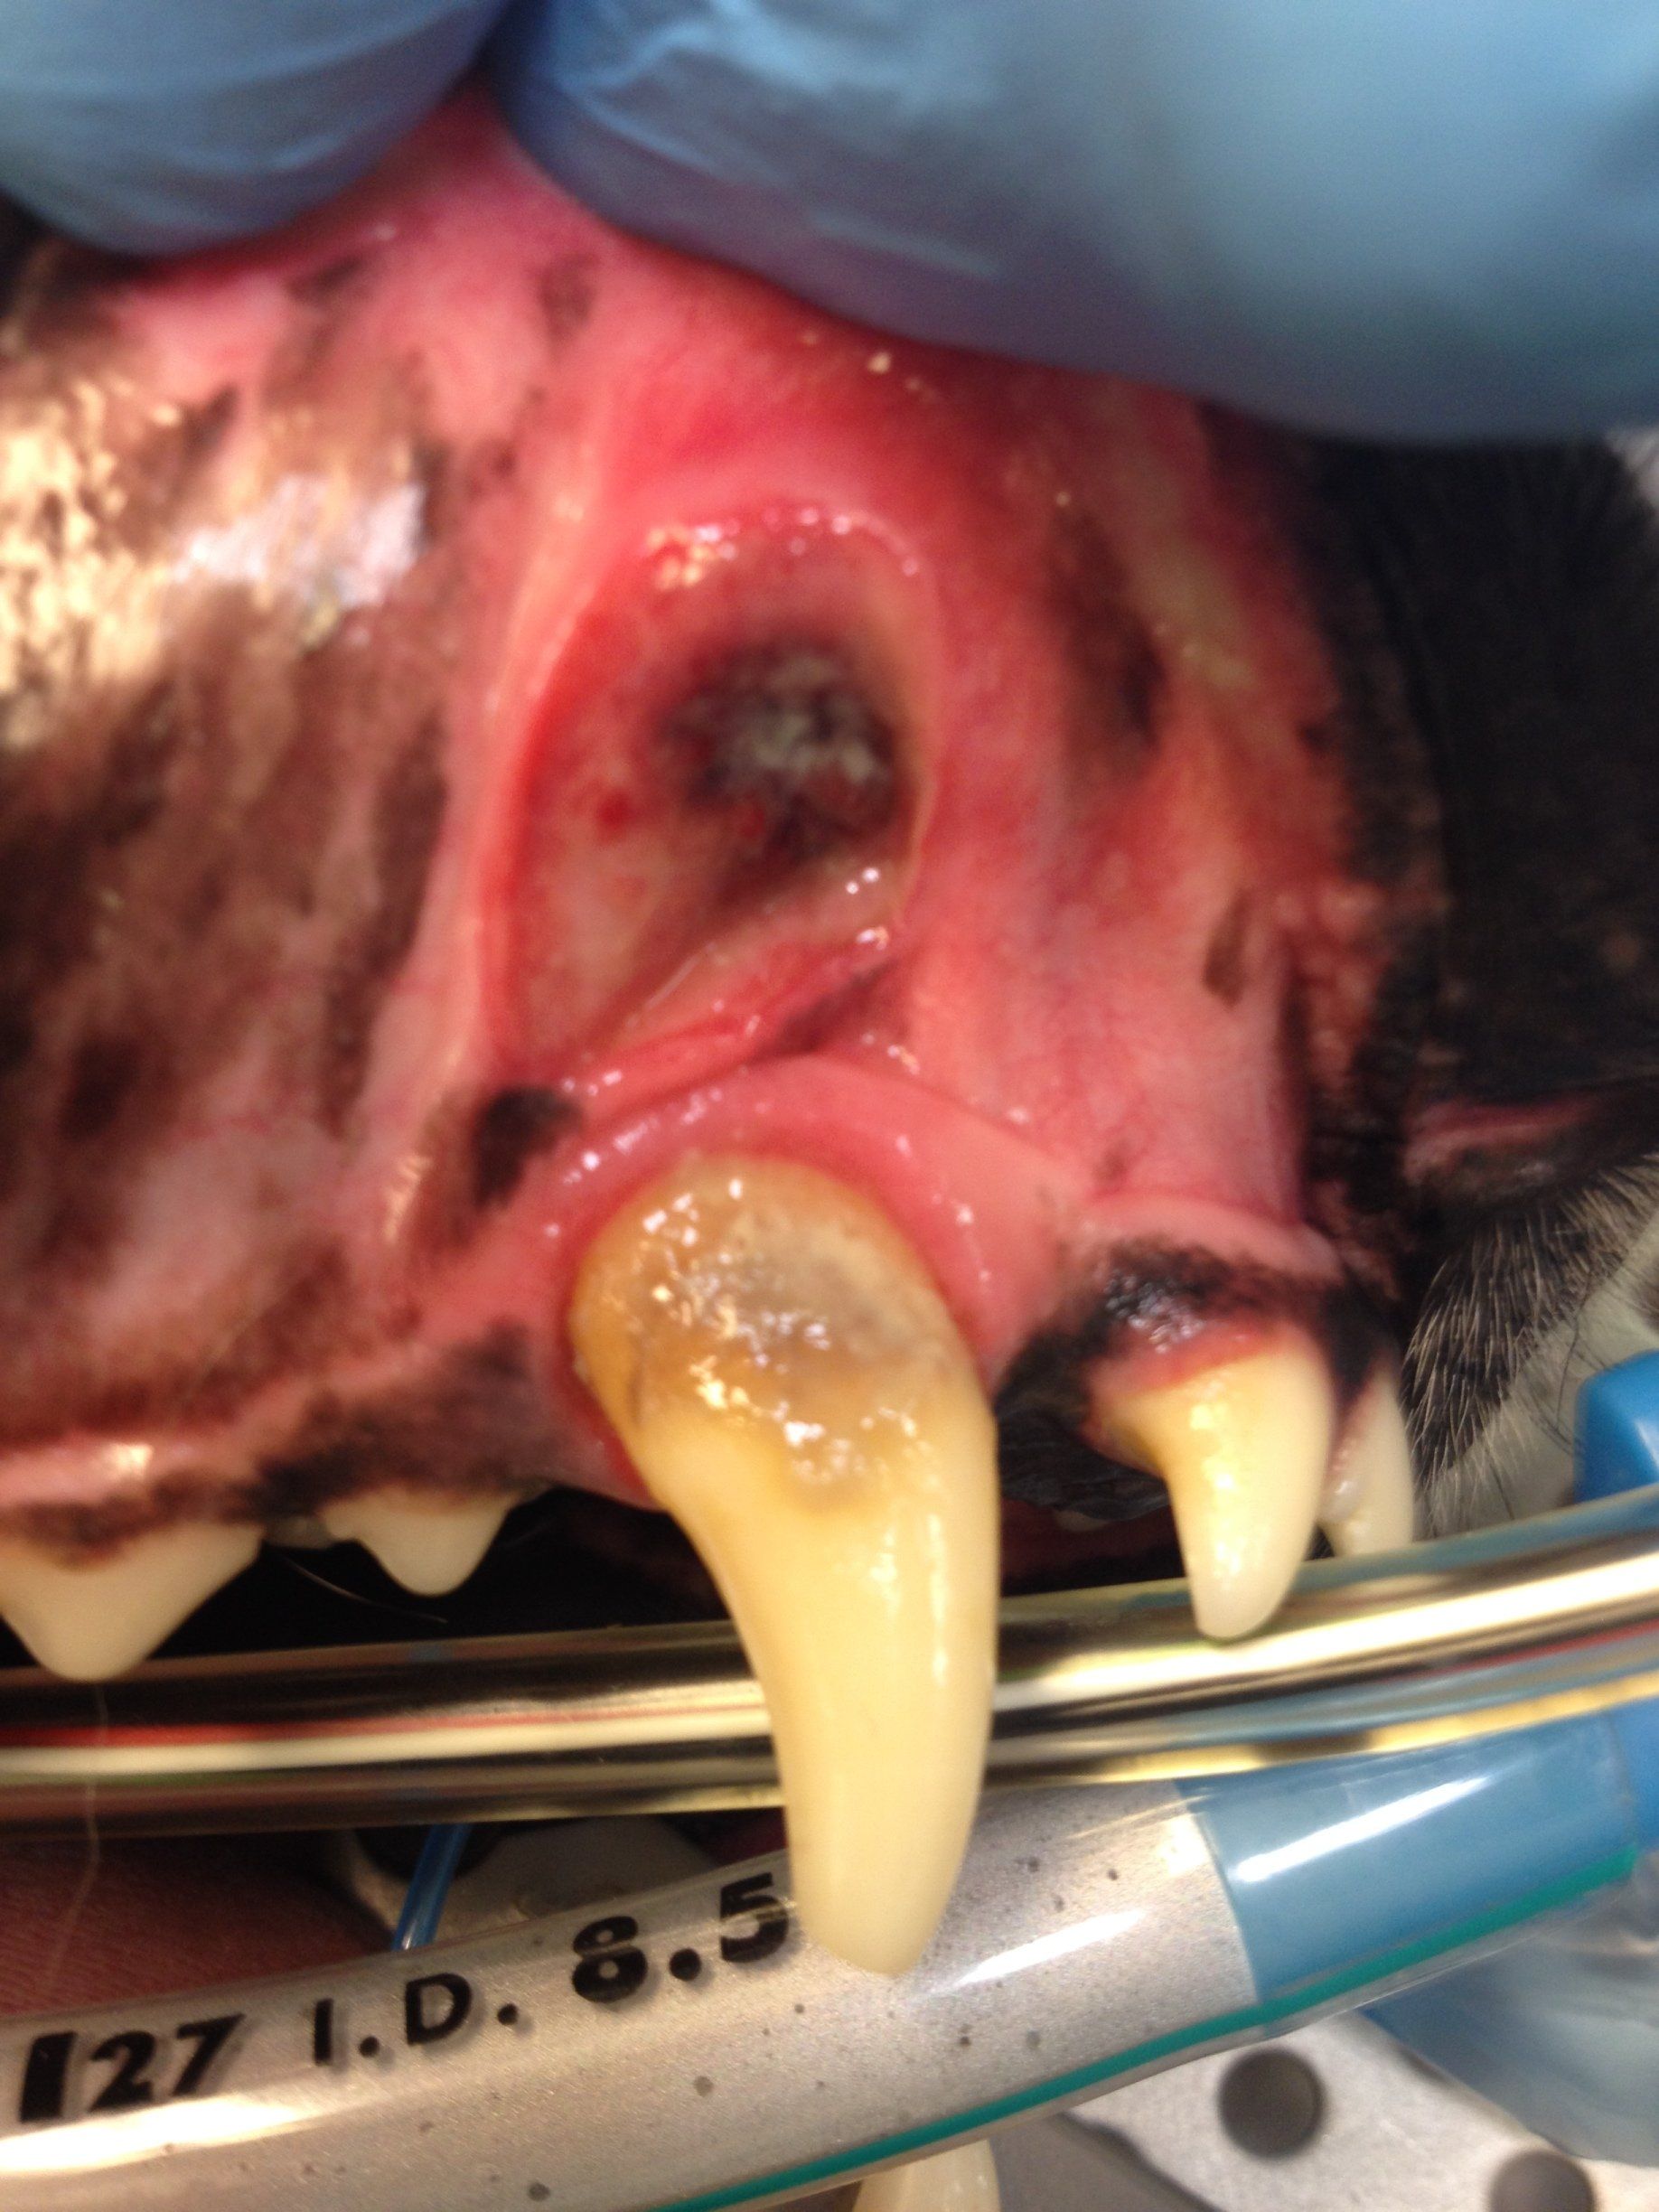

Wortelpunten verwijderen, na een niet goed uitgevoerde totale gebitsextractie, bij de kat

Op foto 1 en 3

zie je een heel erg ontstoken bekje, het tandvlees in de hele bek is vurig rood en super pijnlijk.

Op foto 5 en 6

zie je het resultaat, netjes gehecht en alle wortelrestanten, snijtanden en hoektanden eruit. 80 % van de katten geeft hierna een heel goede verbetering, bij 20% is de verbetering onvoldoende en is verdere behandeling met medicijnen nodig.

Eten geeft geen problemen zonder tanden en kiezen, muizen vangen wordt wel lastiger...